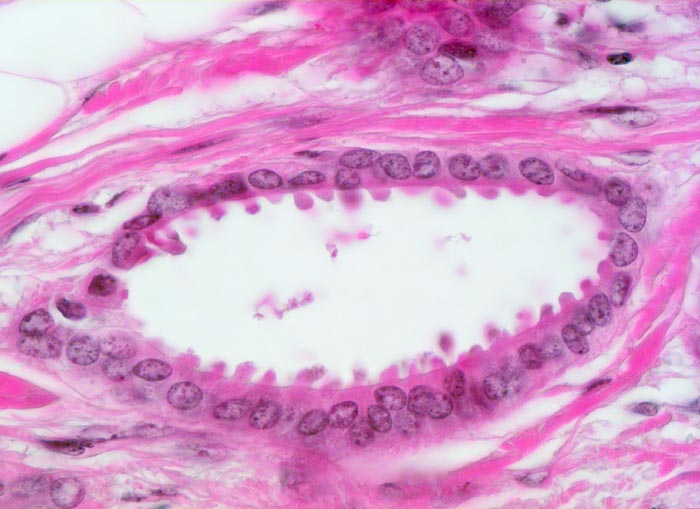

Tubuläre einreihige Karzinomdrüse ohne Basalmembran. Die Tumorzellen zeigen auffallende apikale Ausziehungen des Zytoplasmas (Snouts). Die Tumorzellkerne sind auffallend bland. Eine Myoepithelschicht fehlt.